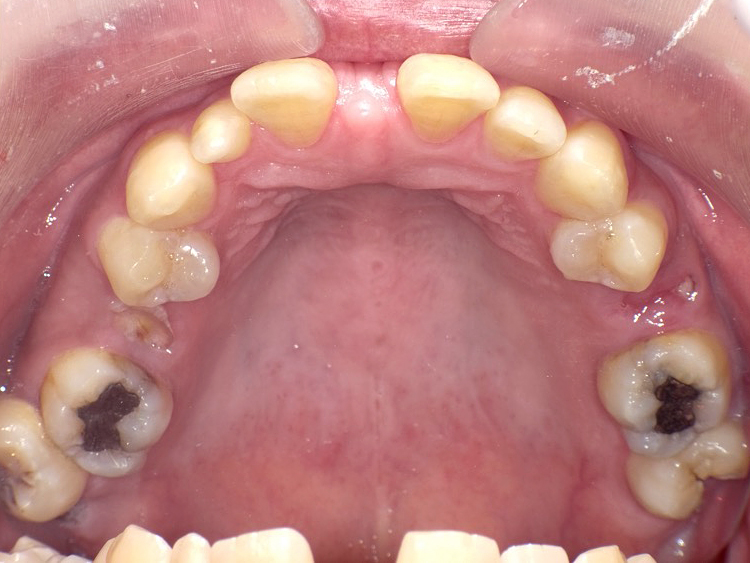

症例3

Before

After

| 主訴 | 上下の歯のガタガタを治したい |

|---|---|

| 年齢 | --- |

| 治療 期間 |

約10ヶ月 |

| 治療 内容 |

インビザラインiGoで上下顎の治療。 狭まっていた歯並びを広げることで、 ガタガタに並んでいた歯を綺麗に並べた。 |

| 治療費 | ¥517,000(税込)+月額調整料 |

| 治療のリスク | 歯と歯の間を削ることでスペースを確保するので、 場合によっては歯が染みる症状が出ることがある。 |